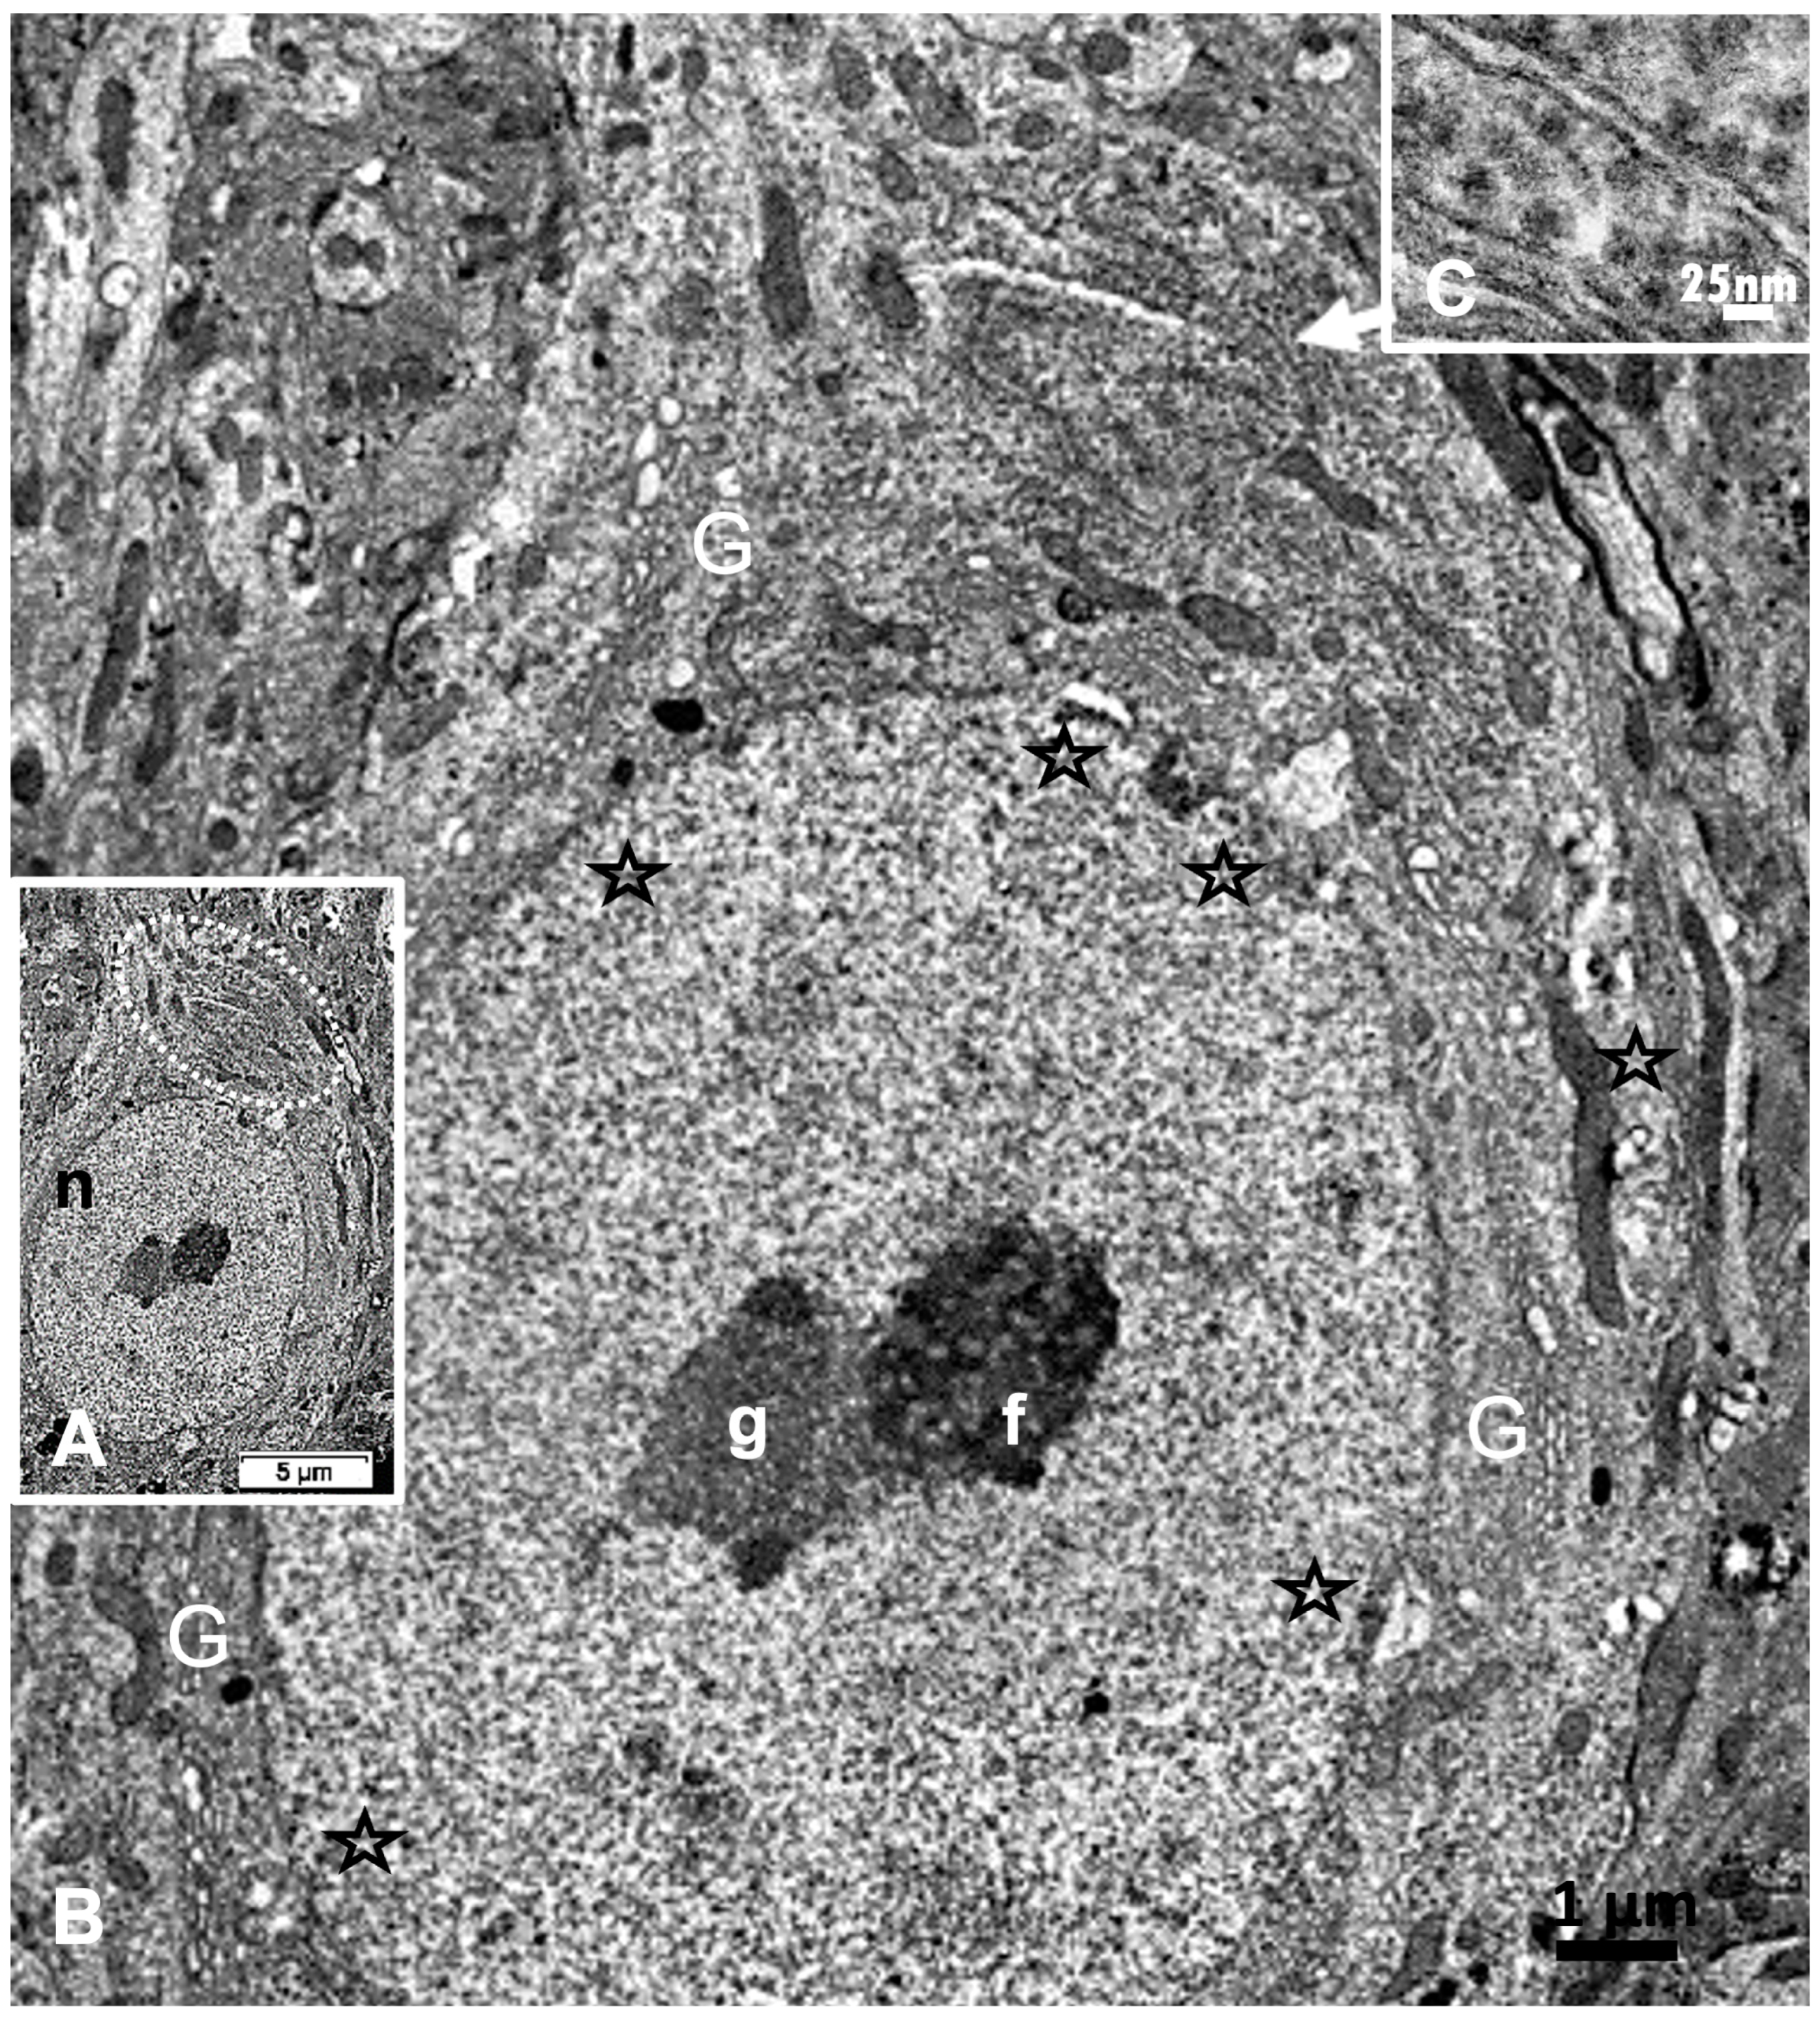

2.2. The ARL13B Labeling and the Resilient ODS Thalamic Nerve Cell Bodies

2.4. ARL13B in ODS12h: LM and TEM Aspects of Neuron Extensions

2.5. ARL13B Label in ODS48h: LM and TEM: A Primary Cilium Emergence